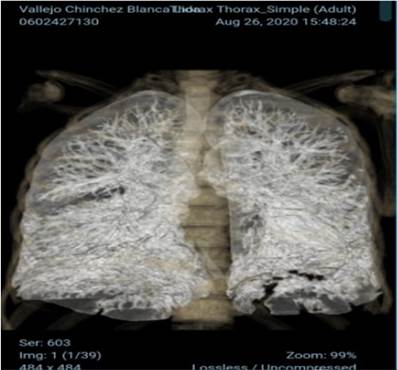

El estudio tomográfico simple muestra múltiples áreas de infiltrado alveolar en vidrio esmerilado, de ubicación periférica subpleural y central en lóbulos superiores asociándose a áreas de engrosamiento septal postrobasal bilateral a predominio izquierdo, hallazgos en relación con neumonía multifocal atípica característico de COVID 19. CORADS 5 (Figura1).

Figura 1 Estudio tomográfico simple.

Estudio tomográfico simple que muestra múltiples áreas de infiltrado alveolar en vidrio es esmerilado, hallazgos en relación con neumonía multifocal atípica característico de COVID 19. CORADS